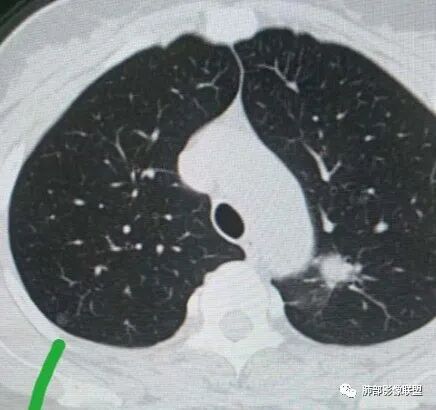

左肺上叶实性结节,光滑,支气管血管贴边,晕,强化持续。两年前就有,考虑psp。另外左肺上叶纵膈侧胸膜下及中带两处混合磨玻璃结节,考虑原位和微浸润可能,需要随访看看。

左肺上叶实性结节,边缘光滑清晰,血管贴边,渐进性延迟强化,密度均匀,考虑PSP.

贴边血管征,强化延迟,考虑PSP

左肺上叶实性结节,边缘光滑清晰,血管贴边,渐进性延迟强化,密度均匀,考虑PSP.但是强化幅度不够,需要鉴别早期肺癌

总共三个结节最大的靠后,有血管贴边征,渐进性明显强化,考虑PSP可能大靠前部中等大小结节考虑MIA靠中部最小的那个结节AAH或者慢性炎症均有可能

首先考虑PSP,周围可疑磨玻璃,鉴别恶性病变

中年女性,左肺上叶实性圆形结节,边缘有晕,血管及支气管贴边,强化尚均匀,渐进性明显强化,考虑为PSP可能

晨读,左上肺实性结节,边缘较规整,密度较均,病灶部分周围有晕,血管贴边,强化呈渐进性,首先考虑psp

左肺实性结节,边界清楚,血管贴边,强化,考虑良性,psp

这个支气管远段没走出来,病变有分叶,周围有磨玻璃,考虑腺癌

中年女性,体检发现。胸部CT示左肺上叶尖后段结节,边界清楚,边缘无分叶,邻近支气管无受压及阻塞;纵膈窗显示结节密度均匀,增强扫描中度渐进性均匀强化,未见坏死及空洞,考虑良性。结节周围可见磨玻璃晕征,并见血管贴边征,考虑硬化性肺细胞瘤(PSP)。

左肺上叶前段可见一磨玻璃结节,边界清,可见小叶间隔阻挡、毛刺 、胸膜牵拉,考虑微浸润腺癌。左肺上叶尖后段可见一实性结节影,边缘光整,光滑浅分叶,周围可见晕征,增强扫描明显延迟强化,可见血管贴边征,结节内未见气管及血管影,女性,考虑PSP

45岁女性,无症状。CT:左上叶前段见一小磨玻璃结节,边请,似有毛刺,边缘见月芽铲,考虑AIS→MIC可能;左上叶尖后段见一圆形实性结节,边清,无分叶,见血管及支气管贴边,增强后延迟强化,考虑良性结节,PSP可能性大,稍不放心的地方局部边缘见边界清楚的磨玻璃影,注意鉴别恶性肿瘤。

左肺上叶两个结节,磨玻璃结节边界清楚,部分收缩,有毛刺,有月牙产征(微浸润性腺癌),另一个实性结节,边缘部分平直,血管部分增粗,支气管似有穿行病灶内,有尖状棘突,毛刺,增强后血管贴边,渐进性强化,里面似有低密度坏死,考虑:PSP,IMT鉴别类癌

女性,右上肺实性结节,边清光滑,无分叶,渐进中度强化,首先支持psp

左肺上叶实性圆形结节,边缘光滑无毛刺分叶,血管贴边,考虑PSP,另两处磨玻璃结节考虑恶性

中年女性,肺结节病史2年。左肺上叶实性结节,下方支气管似有阻塞,边缘见锁条,血管贴边但移位不明确,渐进性延迟强化,密度较均匀,边缘可见边界清楚GGO,平时工作会首先警惕腺癌。病史2年,附近有小病灶,鉴别炎性肉芽肿,psp

中年女性,左肺上叶实性结节,边缘光滑清晰,平直征,渐进性强化,密度均匀,考虑炎性肉芽肿,鉴别PSP

左肺上叶弓旁结节,边缘光滑,支气管血管贴边,延迟强化,周围考虑出血晕,考虑psp,前方两个磨玻璃结节,右肺尖磨玻璃结节,随访观察

中年女性,左肺上叶实性圆形结节,大结节磨玻璃部分清楚,部分模糊,边缘模糊,血管及支气管贴边,强化尚均匀,渐进性明显强化,周围有一更小结节,周围有晕,考虑为炎性肉芽肿。前部一磨玻璃结节,边界清楚,有一定的收缩力,较小,考虑为MIA可能

左肺上叶尖后段实性结节,周围可见边界清晰ggo,渐进性强化,强化均匀;双上肺多大ggo,一元考虑恶性可能性大,其中左肺尖后段实性结节与psp鉴别

左肺上叶前段可见一磨玻璃结节,胸膜牵拉,考虑微浸润腺癌。左肺上叶尖后段可见一实性结节影,边缘光滑浅分叶,周围可见晕征,增强扫描明显延迟强化,可见血管贴边征,结节内未见气管及血管影,女性,考虑PSP。

左上肺近纵隔圆鼓结节,结节边界清楚,结节外周有境界清楚的磨玻璃,,有粗短毛刺和长毛刺,有胸膜凹陷,其内侧的支气管观察受限,建议薄层连续观察。综合考虑:腺癌

左肺上叶实性结节,光滑,晕,渐进持续强化,血管贴边,尾征,虑psp。另左肺上叶纵膈胸膜下磨玻璃结节收缩力强,胸膜牵拉,考虑腺癌,中带磨玻璃结节细节手机不好看,随访!